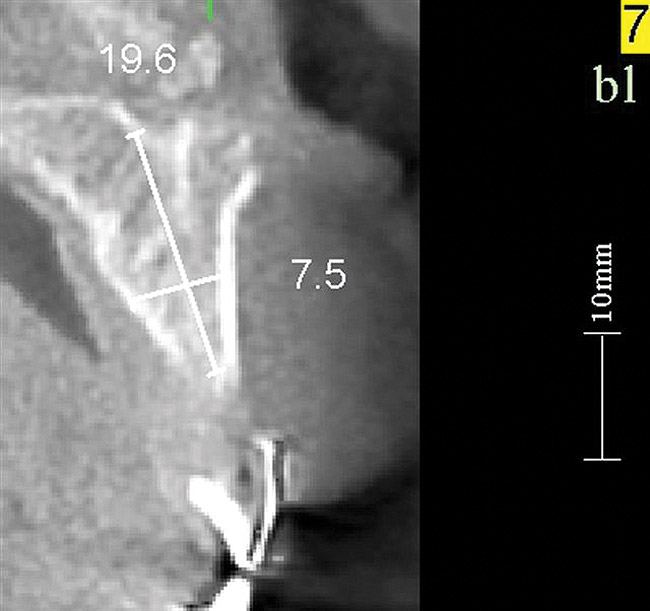

Figure 17   Volumetric characterization of the residual alveolar ridge using CBCT: Fig 17 The coronal section of the maxilla reveals the cortical structure of the alveolar ridge associated with the missing right central incisor at the mid-root level. The buccal plate is identifiable and is characterized by little resorption. Fig 18  The saggital section of the maxillary alveolar ridge is displayed in relationship to the planned contour of the eventual implant crown. Fig 19 Importing DICOM files into planning software permits evaluation of the implant, abutment, and crown relationships with existing bone. These images readily characterize both the possible 6-mm mesiodistal width and the possible displacement of the implant 3-mm apical and 2-mm palatal to the planned gingival zenith.

Figure 18    Volumetric characterization of the residual alveolar ridge using CBCT: Fig 17 The coronal section of the maxilla reveals the cortical structure of the alveolar ridge associated with the missing right central incisor at the mid-root level. The buccal plate is identifiable and is characterized by little resorption. Fig 18  The saggital section of the maxillary alveolar ridge is displayed in relationship to the planned contour of the eventual implant crown. Fig 19 Importing DICOM files into planning software permits evaluation of the implant, abutment, and crown relationships with existing bone. These images readily characterize both the possible 6-mm mesiodistal width and the possible displacement of the implant 3-mm apical and 2-mm palatal to the planned gingival zenith.

Volumetric imaging offers several advantages, including the 3-dimensional (3-D) assessment of the residual alveolar ridge, as well as sufficient resolution of the adjacent teeth to assess bone levels and periapical lesions. CBCT imaging offers access to volumetric imaging with the advantage over medical CT imaging of reduced radiation dose.10 A CBCT image permits the careful measurement of mesiodistal osseous dimension, buccolingual osseous dimension, and occlusogingival dimension of the alveolus, as well as the edentulous space (Figure 17 through Figure 19). The Rules of Six are readily interpreted from CBCT images. Using the Rules of Six, however, does not require that a CBCT image be produced.

Imaging of the proposed crown contour in the volumetric image permits the linear measurement of the located zenith to the bone crest in three dimensions (Figure 18). Thus, the desired 3-mm apical displacement and 2-mm palatal displacement of the implant/abutment interface can be evaluated. This rule serves as both a therapeutic guide—determining where the implant should be placed—as well as a diagnostic guide—determining whether there is enough bone to permit ideal implant placement. When viewing the linear relationship of the existing bone crest to the gingival zenith, the presence or absence of bone at this location offers direction in clinical decision-making. If ideal esthetics is desired and insufficient bone volume is observed, then the decision to perform bone augmentation can be made. If there is excess bone, the decision to place the implant in a subcrestal position can and should be made.